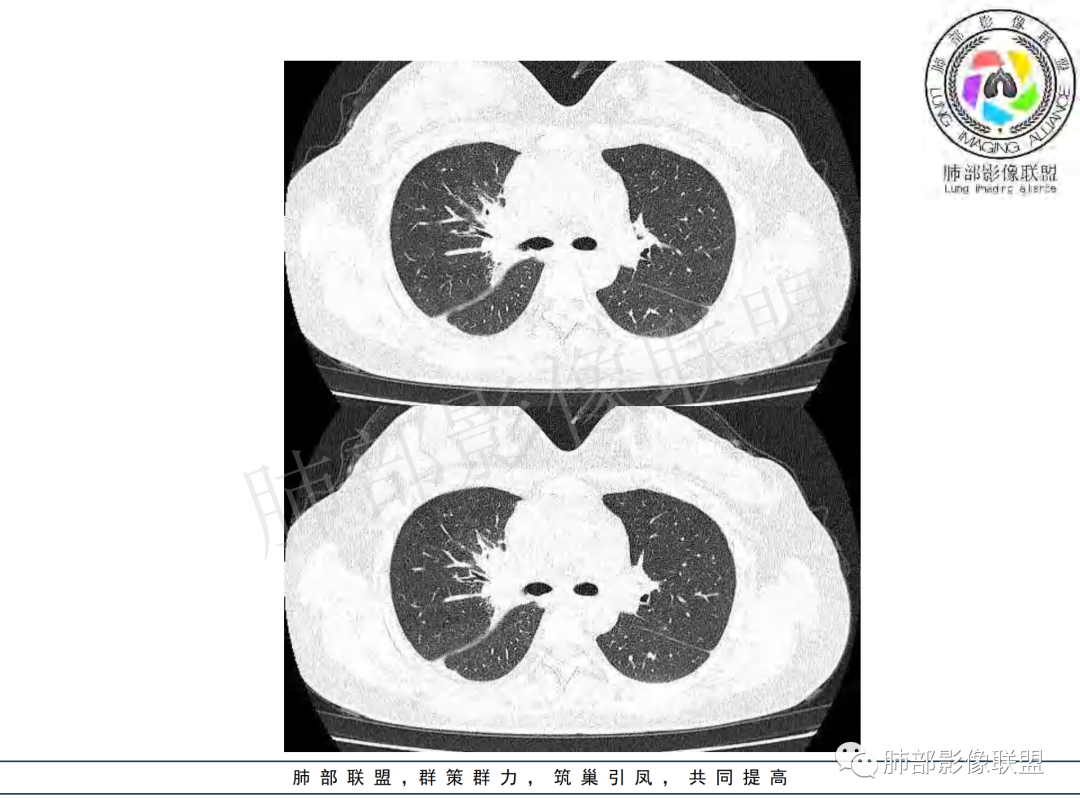

右肺肺门旁肿块,右肺中间段支气管腔内结节,增强强化不均;纵隔多发淋巴结环形强化,右侧少量胸腔积液,临床发热入院,考虑结核,鉴别肿瘤。

右肺门增大,远端花花草草不明显,支气管管壁增厚,纵隔淋巴结环形强化,年龄,病程,考虑炎性病变,结核可能,有个层面支气管截断,有强化,鉴别粘表。

女,20,病程长达8月,发热、胸痛、右侧胸腔积液病史。胸部CT:右肺门旁不规则肿块影,右中间支气管腔内结节,纵隔多发淋巴结肿大;强化不均匀,灶性坏死灶,环形强化;右侧少量胸腔积液并局部肉芽肿样突起。年轻女性,长病程,多部位,考虑慢性炎症,结核?鉴别肿瘤。

右肺肺门旁肿块,右肺中间段支气管腔内结节,增强强化不均;纵隔多发淋巴结环形强化,右侧少量胸腔积液,考虑结核可能,鉴别肿瘤。

年轻女性,慢性病程,发热、胸痛。右肺门旁不规则肿块影,纵隔多发淋巴结肿大;强化不均匀,环形强化;右侧少量胸腔积液;首先考虑结核,鉴别肿瘤,结节病。

女性,20岁。高热、畏寒。右肺上叶近肺门区不规则肿块,周围斑点、片小结节影伴肿大淋巴结,肿块包绕并突入右主支气管腔内,增强后肿块不均匀强化,淋巴结环形强化中心低密度,考虑结核。

本例患者,年轻女性,慢性病程,多次抗感染治疗效果不佳,实验室检查示白细胞及中性粒细胞不高,不支持普通细菌感染,虽然肺泡灌洗液X-Pert检测阴性,结合患者胸部CT结核感染亦不能排除,胸部CT主要表现为右侧肺门及纵隔淋巴结肿大,仔细观察不难发现右中间支气管内新生物凸向管腔内,增强扫描,右肺门(10R)及纵隔淋巴结(2R,4R)明显不均匀强化,内部呈不规则低密度无强化区,被周边高强化区包绕(环形强化)的特点,首先应当想到纵隔淋巴结结核诊断。淋巴结分布亦不符合肺部恶性肿瘤迁徙途径。